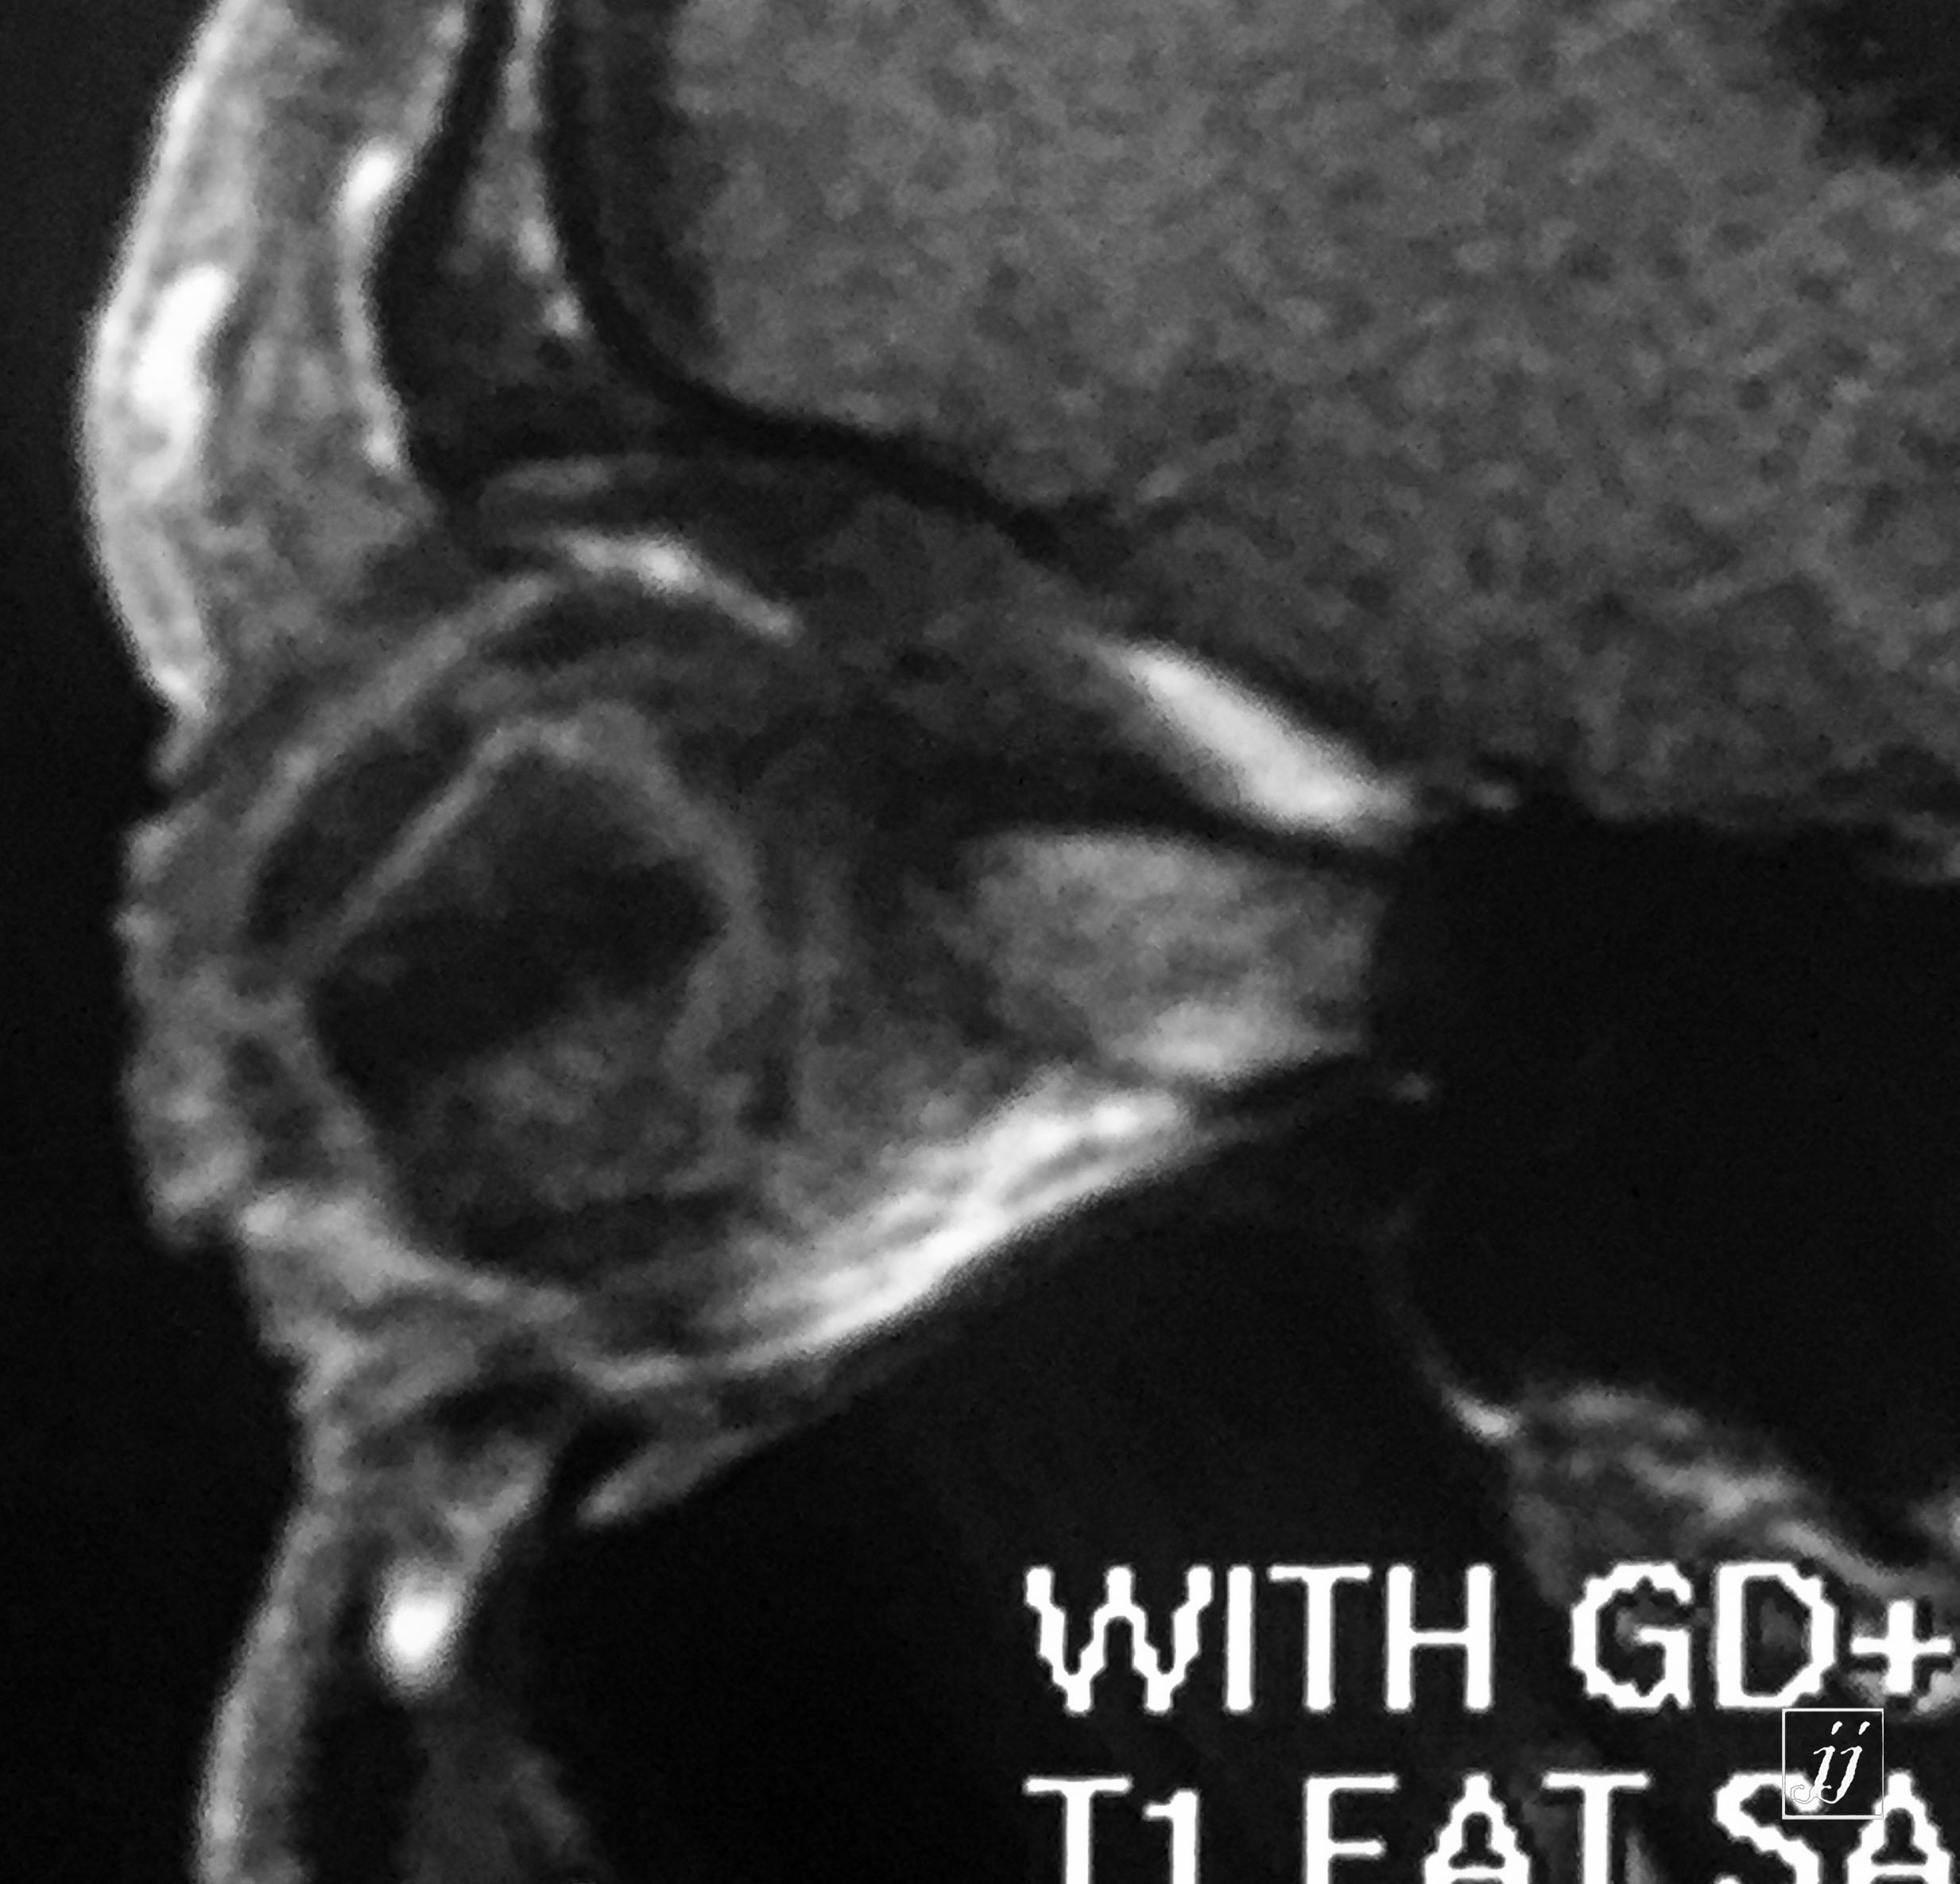

Orbit- vitreous detachment (13)